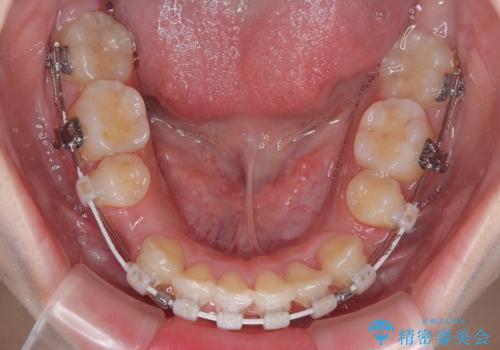

- 矯正装置

- 審美装置

- 治療期間

- 2年

口元の突出感は気になっていないものの、デコボコを解消すると口元が前方に突出する可能性があるため、上下左右の第一小臼歯4本を抜歯して、ワイヤー装置にて矯正治療を行うこととしました。